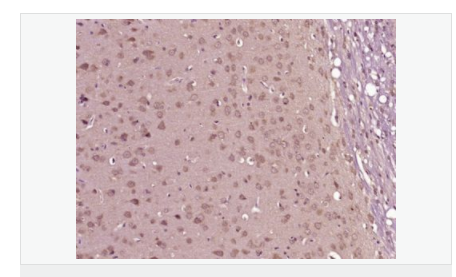

交叉反應:Mouse,Rat(predicted:Human,Dog,Pig,Cow,Horse,Rabbit,Sheep) 推薦應用:WB,IHC-P,IHC-F,ICC,IF

| 產品應用 | WB=1:500-2000 IHC-P=1:100-500 IHC-F=1:100-500 ICC=1:100-500 IF=1:100-500 (石蠟切片需做抗原修復) not yet tested in other applications. optimal dilutions/concentrations should be determined by the end user. |